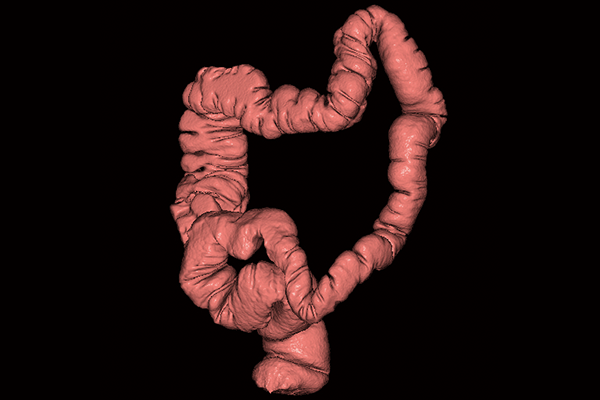

SYNAPSE 3D’s advanced image analysis technology aids clinical interpretation, reporting, and treatment planning. Especially, automatic organ segmentation technology enables fast and effective workflow, powered by REiLI, FUJIFILM's AI brand. With a series of high-tech applications developed in collaboration with clinical specialists, SYNAPSE 3D quickly and accurately delivers imaging result that promotes effective care collaboration.

REiLI makes it happen to extract organs and simplify your work.

Colon